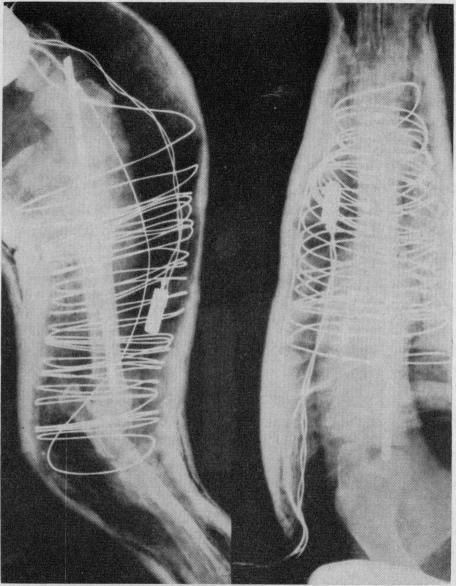

The effect of heat on the healing of fractures: a preliminary experimental report.

Can Med Assoc J. 1967 Aug 5;97(6):274-80.